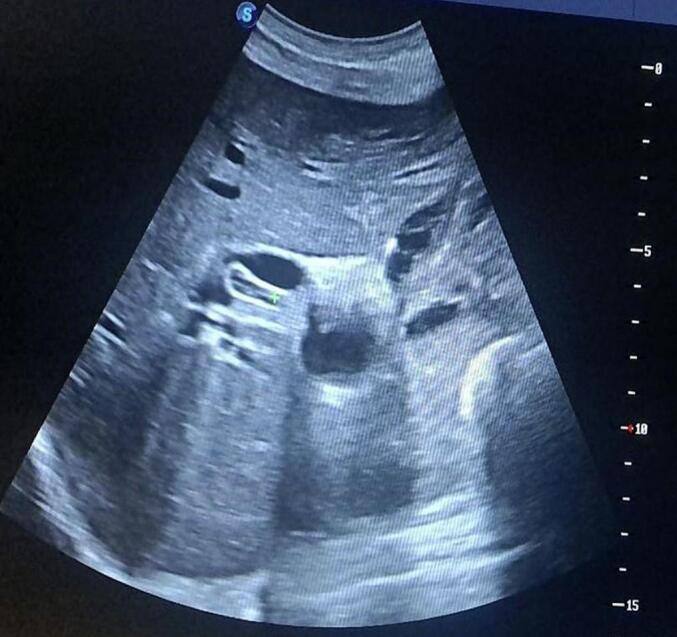

CASE PRESENTATION

A 28-year-old female farmer from a rural area presented with a one-year history of intermittent right upper quadrant pain, worsened by fatty meals. Her symptoms progressed a week before presentation to include fever, jaundice, dark urine, and pruritus. Examination revealed a positive Murphy sign and jaundice, with laboratory results showing leukocytosis and elevated bilirubin. Imaging confirmed biliary ascariasis with choledocholithiasis and ascending cholangitis. Intraoperatively, a sealed perforation of the gallbladder was found alongside a dead Ascaris and multiple stones in the common bile duct (CBD). Surgical intervention included removal of the worms and stones, cholecystectomy and CBD irrigation. Postoperative recovery was uneventful, and the patient was discharged with antihelminthic therapy.

一名来自农村地区的28岁女性农民,有一年间歇性右上腹疼痛病史,油腻餐后加重。在就诊前一周,她的症状进展,出现发热、黄疸、深色尿和瘙痒。检查发现墨菲氏征阳性和黄疸,实验室检查结果显示白细胞增多和胆红素升高。影像学检查证实为胆道蛔虫病合并胆总管结石和化脓性胆管炎。术中发现胆囊有一处封闭性穿孔,同时在胆总管内有一条死蛔虫和多个结石。手术干预包括取出蛔虫和结石、胆囊切除术及胆总管冲洗。术后恢复顺利,患者接受抗蠕虫治疗后出院。

胆道蛔虫病是胆道梗阻的少见原因,但可导致胆管炎和胆囊穿孔等严重并发症。诊断通常依靠临床症状,并由超声和CT影像学检查辅助。治疗包括药物和手术方法,如使用抗生素以及手术取出蛔虫和结石。根据奈迈尔分类,该病例属于II型胆囊穿孔,即脓肿被粘连包裹。